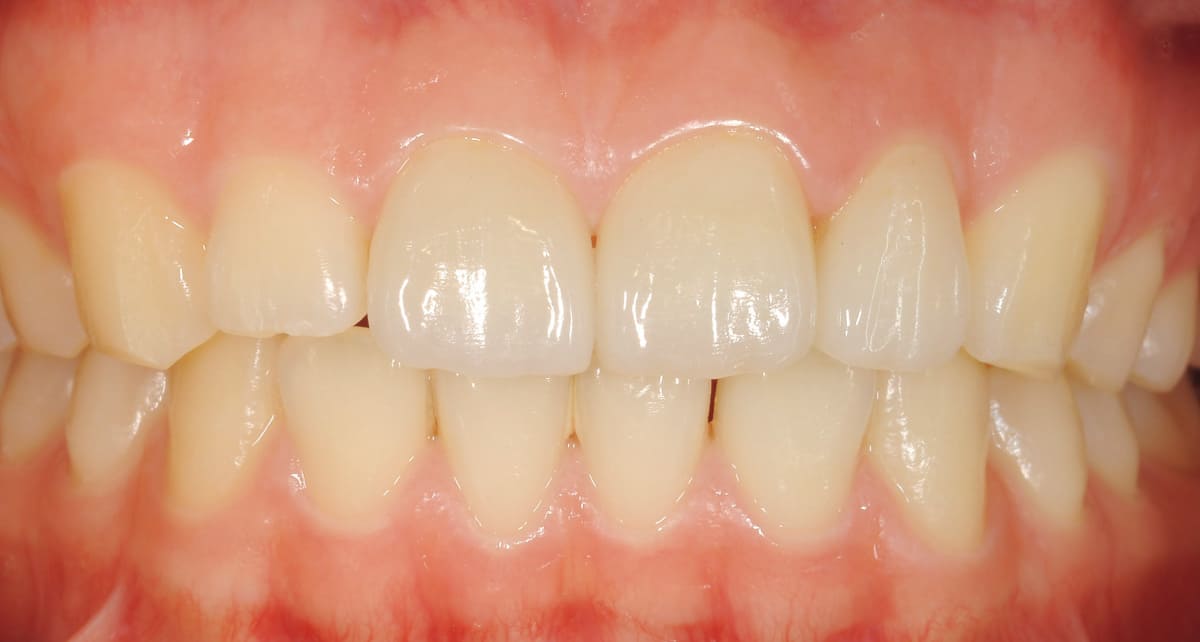

ダイレクトボンディング|ペースト状の材料を歯に盛り付けるだけ。

Before

After

むし歯や前歯の隙間、欠けた歯を修復する治療。セラミックとプラスチックの混合物であるレジンというペースト状の材料を直接歯に盛り付ける。クラウンのように型取りする必要もないので短期間で済み、歯を削る範囲も最小限。

【料金】3万円〜

【治療期間】1日〜2週間程度